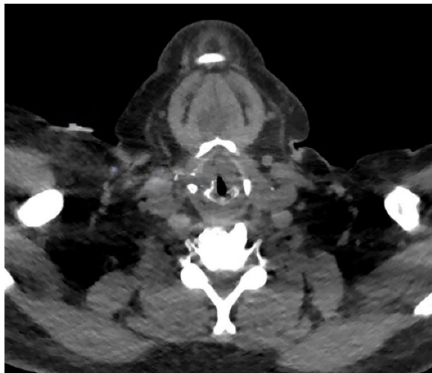

24岁女性患者因持续6周的发音困难(dysphonia)和吞咽痛(odynophagia)就诊,有4年高功率电子烟使用史。喉镜检查可见声门上区和声门区大面积黏膜坏死伴溃疡形成。

病例2:男性患者气道危机

30岁男性在5年电子烟使用后出现进行性喘鸣(stridor),组织病理显示非特异性坏死性炎症。